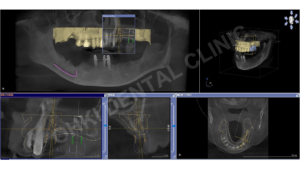

【症例紹介】インプラント治療|歯根破折による多数歯欠損リスクを回避し噛む機能を回復

残存歯の健康寿命を延ばす インプラント治療によって、重度の歯根破折を伴う欠損部位に噛み合わせを支える柱を再建し、残存歯の...